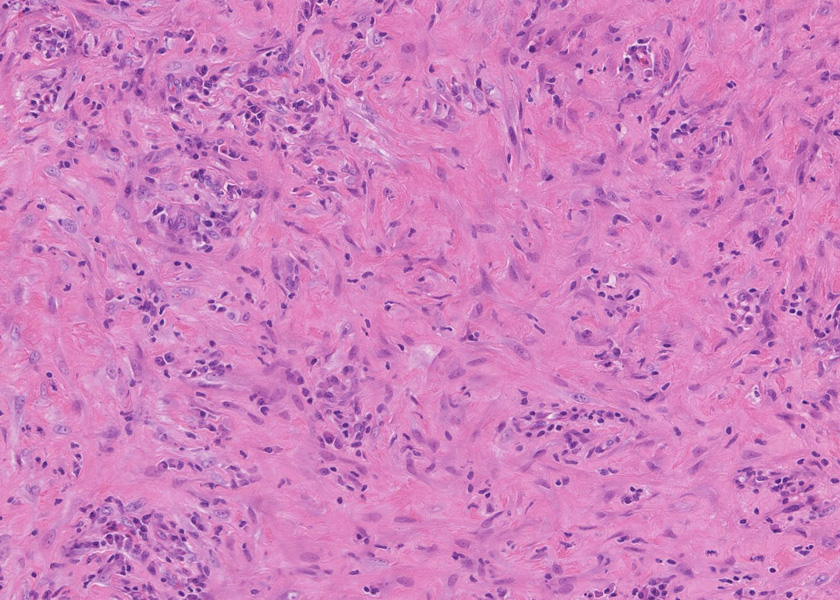

膵腺房間質にリンパ球, 形質細胞, 好中球の炎症細胞浸潤が認められる。

線維化組織に類円, 葉巻型淡明な核の紡錘型細胞が増生している。免染SMA陽性。血管周囲に慢性炎症あり。